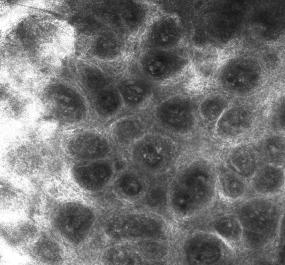

皮肤共聚焦扫描显微镜

Munro微脓肿

Kogoj微脓肿